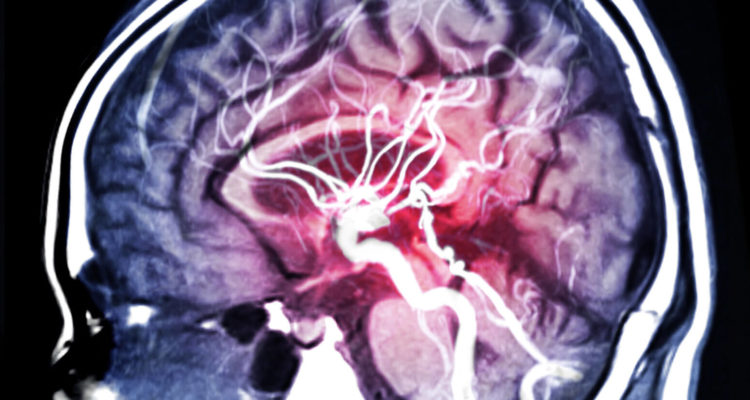

Інсульт виникає, коли мозок не отримує достатньо крові, що позбавляє його кисню і поживних речовин. В результаті клітини мозку відмирають. При цьому дослідження показують, що шанс зіткнутися з інсультом на 80% вище в один і той же час доби.